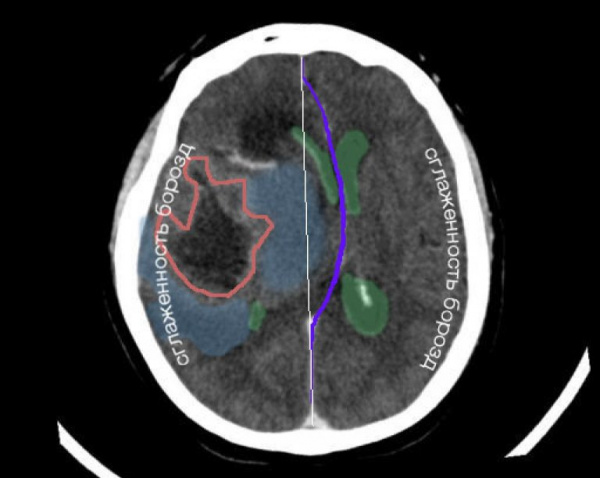

• Подфальксное вклинение:

о Наиболее распространенный тип вклинения

о Смещение поясной извилины под серп

о Компрессия ипсилатерального желудочка и его латеральное смещение с пересечением срединной линии

о Осложнения:

- Ранние: расширение контрлатерального желудочка вследствие обструкции на уровне отверстия Монро

- Поздние: смещение передних мозговых артерий (ПМА) -> компрессия о свободный край серпа → окклюзия → вторичный инфаркт

2. КТ при синдроме дислокации головного мозга:

• Бесконтрастная КТ:

о Смещение желудочков; полное сужение борозд/цистерн

2. Макроскопические и хирургические особенности:

• Выраженный отек-набухание головного мозга

• Компрессия и прижатие извилин о свод черепа

• Сглаженность борозд